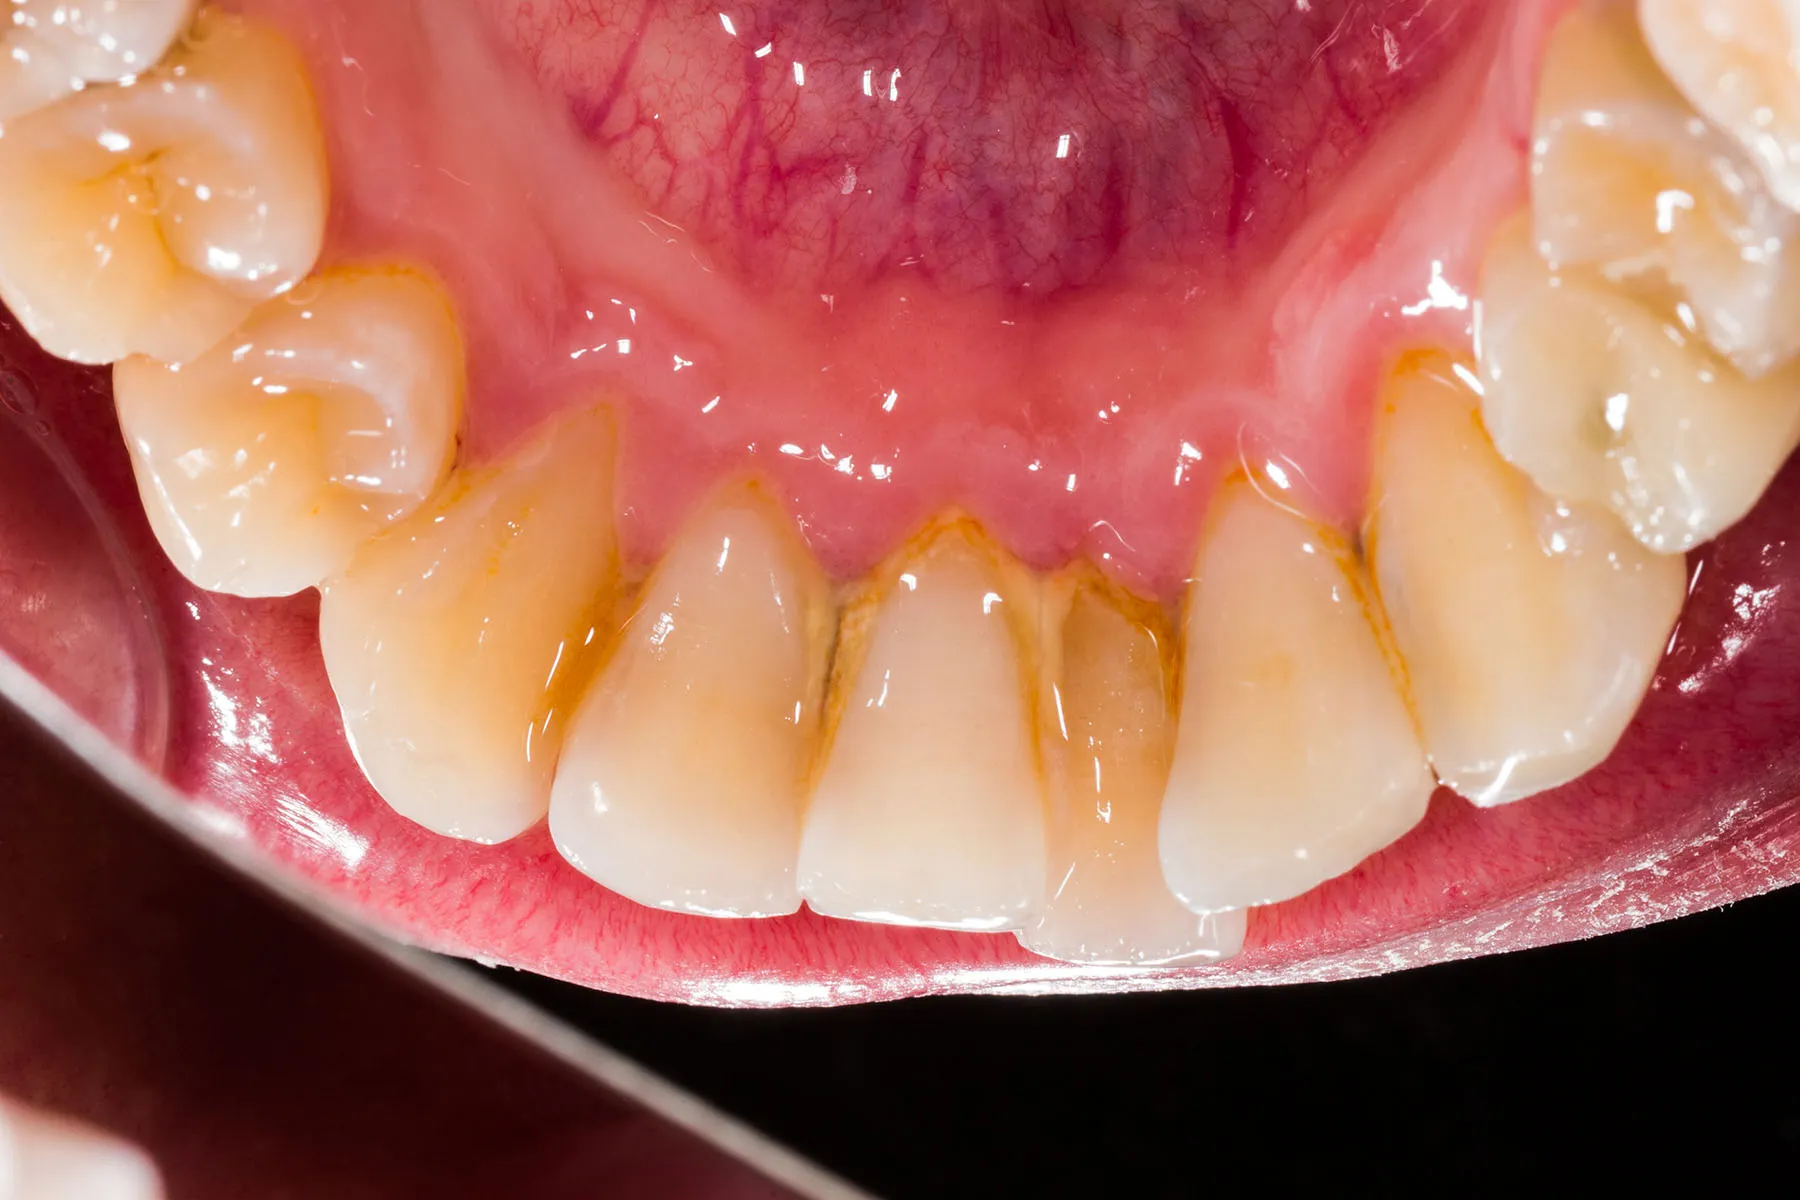

Tartar feels rough, hard, and crusty. - Color

Plaque is usually colorless or pale.

Tartar can appear yellow or brown. - Removal Method